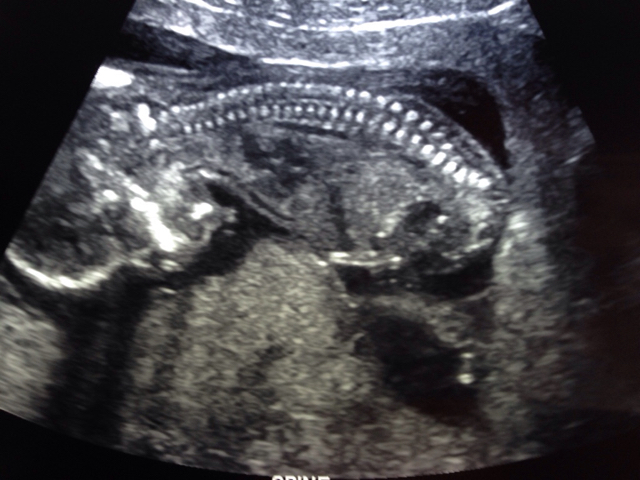

Sorry. These are the only potty shot pictures I have. And these pictures..Attachment 25073 Attachment 25072